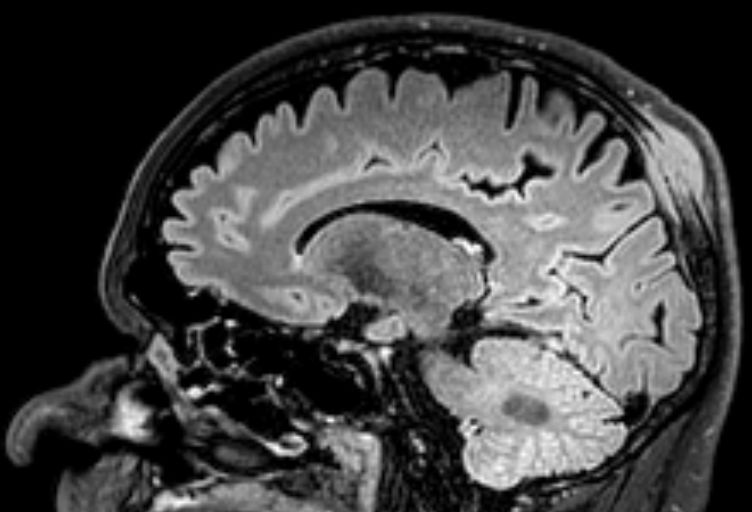

Im T1-gewichteten MRT ist der Tumor

zu erkennen.![]() | ||

Das Flaire-MRT zeigt, dass das Lymphom vom Knochen ausgeht und nach außen und innen wächst.![]() |